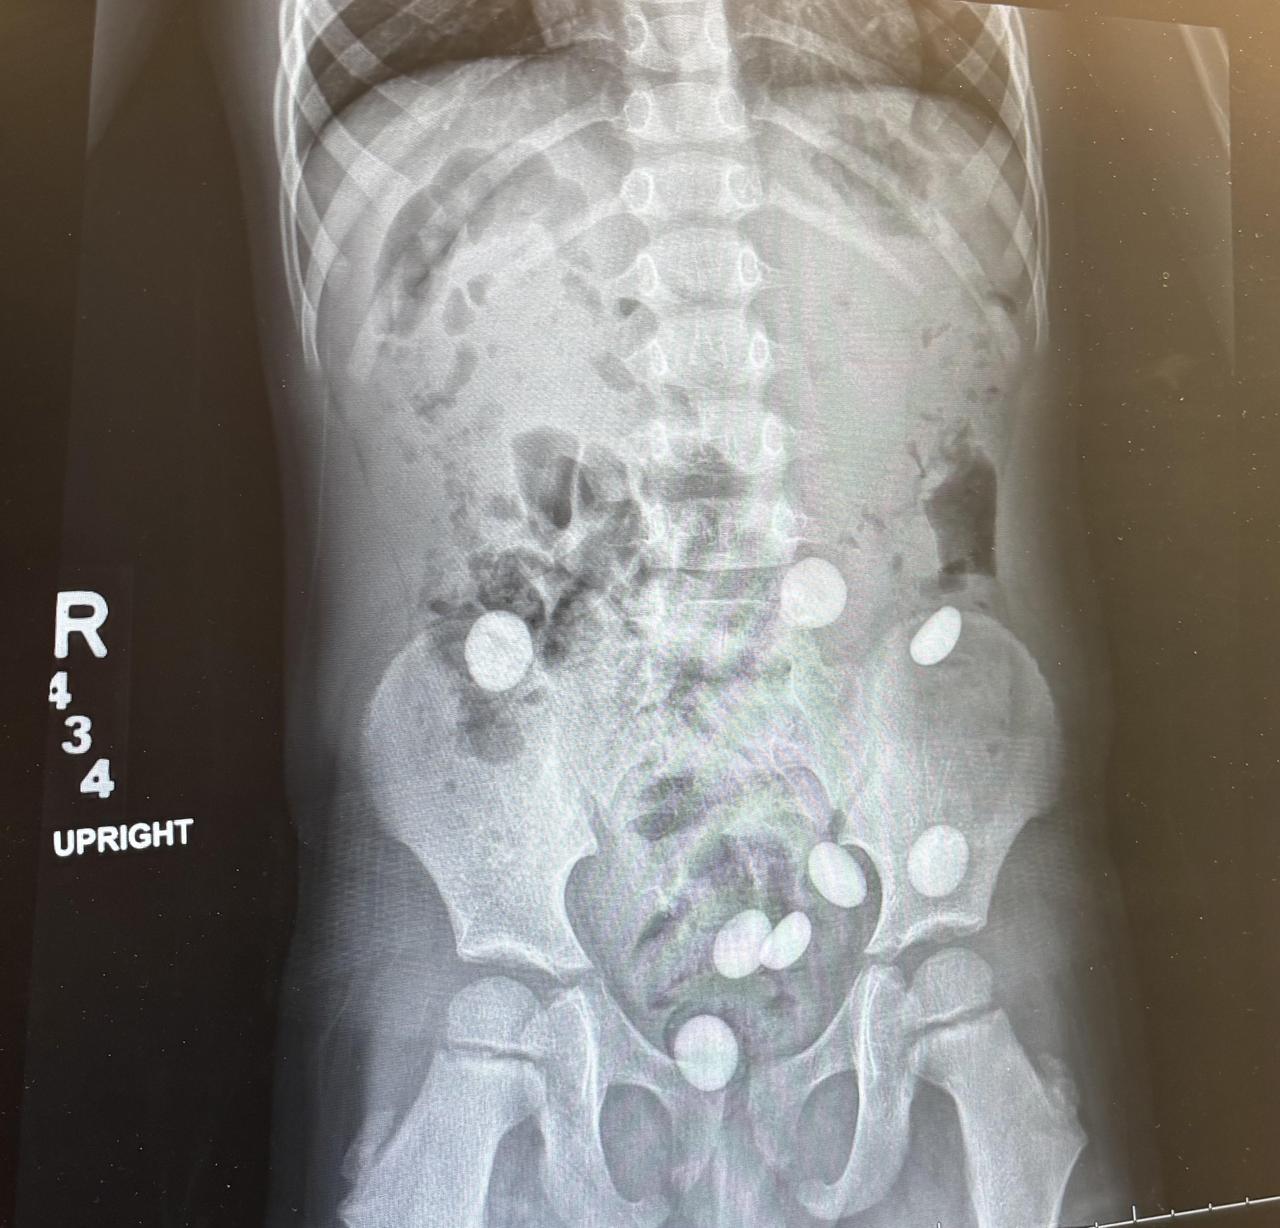

一名幼儿意外吞下8颗弹珠,经过71小时才全部排出,家长不得不仔细检查排泄物确认每颗都已通过。有网友调侃孩子吞下第一颗后觉得味道不错,于是又追加了7颗,还有人分享自己童年吞硬币或拼字游戏棋子的经历。